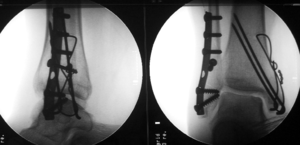

A bimalleolar fracture is a fracture of the ankle that involves the lateral malleolus and the medial malleolus. Studies have shown[1] that bimalleolar fractures are more common in women, people over 60 years of age, and patients with existing comorbidities.[1]

Surgical treatment will often be required, usually an Open Reduction Internal Fixation. This involves the surgical reduction, or realignment, of the fracture followed by the implementation of surgical implants to aid in the healing of the fracture.[2]